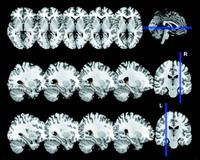

研究人员对受试者进行了测试,并在训练之前、过程中以及结束后对他们的大脑进行了扫描。

研究人员发现,在开始训练之前,具有从业资格的学员的大脑与那些没有从业资格的学员、或非出租车司机的大脑并没有差别。

然而随着出租车司机掌握了更多的信息,他们的海马区也在不断增大,并逐渐改变了他们的大脑。

而不成功的学员的大脑海马区从始至终都是相同的大小,这可能意味着,成功的出租车司机真的拥有一种与生俱来的优势——他们的大脑比别人具有更大的可塑性。

The last decade has seen a burgeoning of reports associating brain structure with specific skills and traits . Although these cross-sectional studies are informative, cause and effect are impossible to establish without longitudinal investigation of the same individuals before and after an intervention. Several longitudinal studies have been conducted ; some involved children or young adults, potentially conflating brain development with learning, most were restricted to the motor domain, and all concerned relatively short timescales (weeks or months). Here, by contrast, we utilized a unique opportunity to study average-IQ adults operating in the real world as they learned, over four years, the complex layout of London's streets while training to become licensed taxi drivers. In those who qualified, acquisition of an internal spatial representation of London was associated with a selective increase in gray matter (GM) volume in their posterior hippocampi and concomitant changes to their memory profile. No structural brain changes were observed in trainees who failed to qualify or control participants. We conclude that specific, enduring, structural brain changes in adult humans can be induced by biologically relevant behaviors engaging higher cognitive functions such as spatial memory, with significance for the “nature versus nurture” debate.